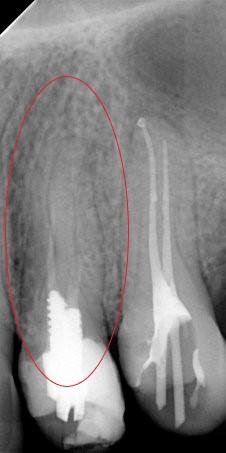

Leczenie kanałowe jest leczeniem skutecznym. Prawidłowe leczenie kanałowe sprawia, że ząb przestaje być ogniskiem zakażenia, a tkanki wokół goją się. Wyleczenie zęba powoduje, że przyczyna choroby tkanek około zębowych [na RTG widzimy jedynie chorobę kości] zostaje usunięta. Eliminacja przyczyny choroby umożliwia gojenie się zmian chorobowych.

Na poniższych zdjęciach RTG – WIDAĆ GOJENIE ZMIAN ZAPALNYCH KOŚCI.

Nie jest prawdą, że leczenie kanałowe w każdym przypadku jest szkodliwe. Ogniskami zakażenia są zęby martwe, nieprzeleczone kanałowo, zęby z nieprawidłowym leczeniem kanałowym i to właśnie one są zagrożeniem i powinny być eliminowane.